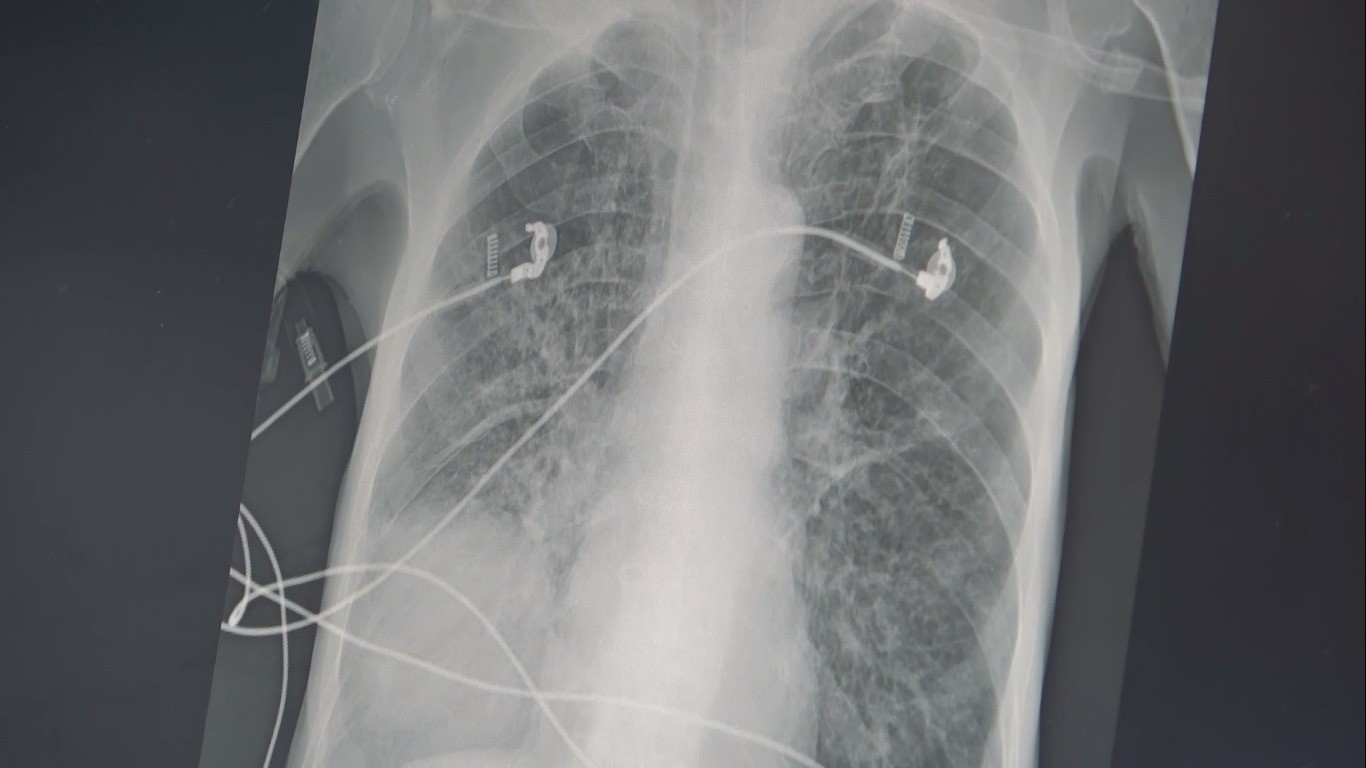

Sigara kullanımın zararlarının insanlara anlatmanın artık etkili olmadığını ifade eden Göğüs Hastalıkları Uzm. Prof. Dr. Şevket Özkaya, balon örneği üzerinde sigaranın verdiği zararı anlattı. Sigara kullanımın ortaokul yaşına kadar düştüğünü söyleyen Prof. Dr. Özkaya, "Ülkemizde 20 yaş üstündeki kişilerin en az yarısı sigara bağımlısıdır ve sigaraya başlama yaşı artık ortaokul çağlarına kadar indi. Sigaranın zararları anlatmak artık insanlarımızı etkilemiyor ama içtiğiniz sigara 2 ölümcül hastalığın yüzde 90 sebebidir. Bunlarda biri KOAH, diğeri ise akciğer kanseridir. Eğer yaşınız 40 üzeri ve içtiğiniz sigara paketi ile kullandığınız yılı çarpar, 20 paket/ yıldan daha fazla ise bu iki hastalık ile her an yüzleşebilirsiniz. KOAH teşhisi alan kişilerin büyük çoğunluğu halen sigara içen veya çok uzun süre sigara içmiş ve bırakmış kişilerdir. Hastalık sinsi ilerlediği için ve sigara bağımlıları öksürük, balgam çıkarma gibi şikayetleri önemsemedikleri için KOAH teşhisi konduğu zaman hastalar akciğer kapasitelerinin önemli bir kısmını kaybetmiş olmaktadırlar" diye konuştu.

Akciğer keseciklerinin tıpkı bir balon gibi olduğuna dikkat çeken Özkaya, "Temiz havayı nefes olarak bu keseciklere aldığınızda şişer ve hava ile dolunca elastik yapısından dolayı içerdeki kirli havayı da tıpkı balonun sönmesi gibi dışarı atar. Bu mekanizma hayat kurtarıcıdır. Ancak sigara içerseniz, kesecik duvarlarınızdaki elastik doku harap olur ve esneme yeteneğini kaybederek tıpkı bu naylon poşet gibi olur ve nefes alırsınız ama balonun elastik yapısı olmadığı için kirli havayı dışarı atamazsınız ve içerde kirli hava kalır. Siz yeni bir temiz havayı nefes le almak istediğinizde keseciklerde temiz havanın gireceği yer kalmayacak ve nefes alamama yani nefes darlığı başlayacak" şeklinde konuştu.

Kişilerin uzun yaşama imkanı da olsa her hücrenin kanserden öleceğini belirten Özkaya, "Sigaranın diğer ölümcül sebebi ise akciğer kanseridir. Biz şunu biliyoruz ki, yaşayan her sağlıklı hücrenin sonu kanser. Eğer diğer hastalıklar, kazalar ve erken ölümler olmasa ve uzun yaşama imkanı olsa her hücre kanserden ölecek. Eğer sigara kullanıyor veya kanserojen maddelere maruz kalıyorsanız, bu kansere yakalanma yaşınızı düşüren bir faktör. Örneğin; 150 veya 170 yaşında akciğer kanseri olacak bir kişi, sigara içtiği için bu yaş 100'e düşüyor. Eğer ailede kanser öyküsü varsa bu yaş daha da düşüyor. Ve 45 yaşından sonra her an kanser gelişmesi ile karşı karşıya kalınıyor. Sigara içmeye hiç başlamayarak bu iki ölümcül nefesten kurtulabilir ya da bırakarak bu iki ölümcül hastalık riskinizi azaltabilirsiniz" şeklinde konuştu.